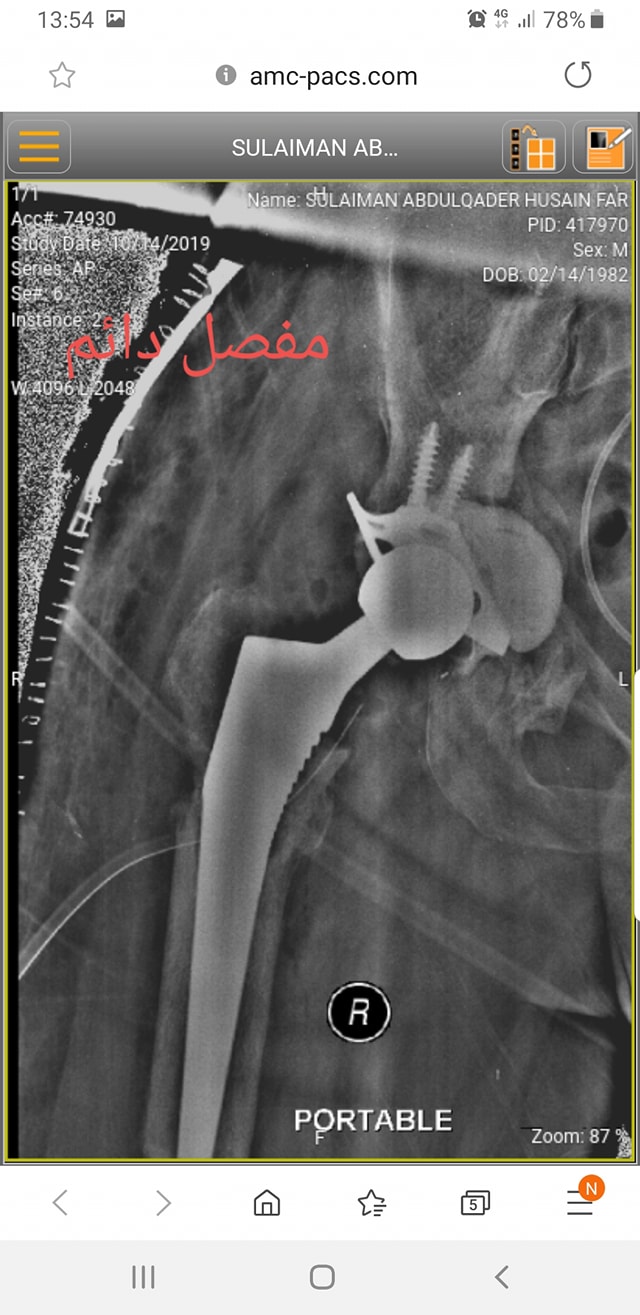

زراعة المفاصل الصناعية ورك و